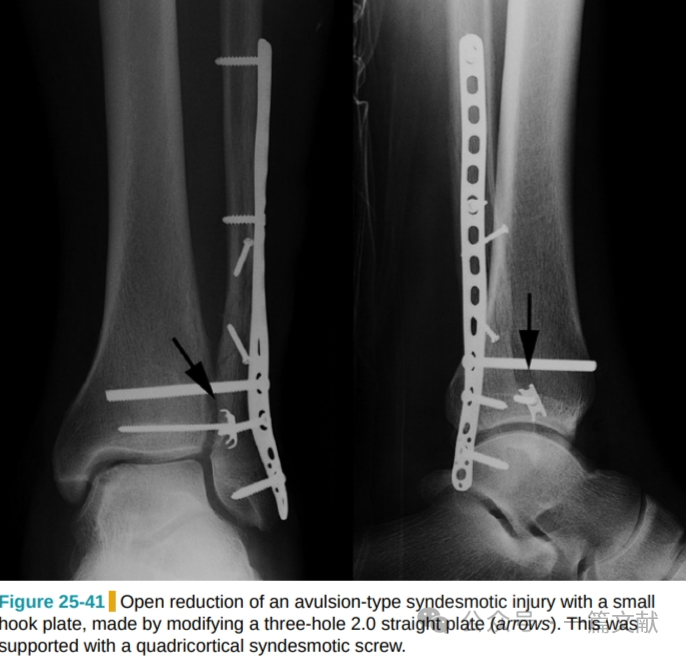

此时建议切开复位并内固定,撕脱骨折块较小时可用小的三孔钢板经加工并折弯后固定,如下图:

图片